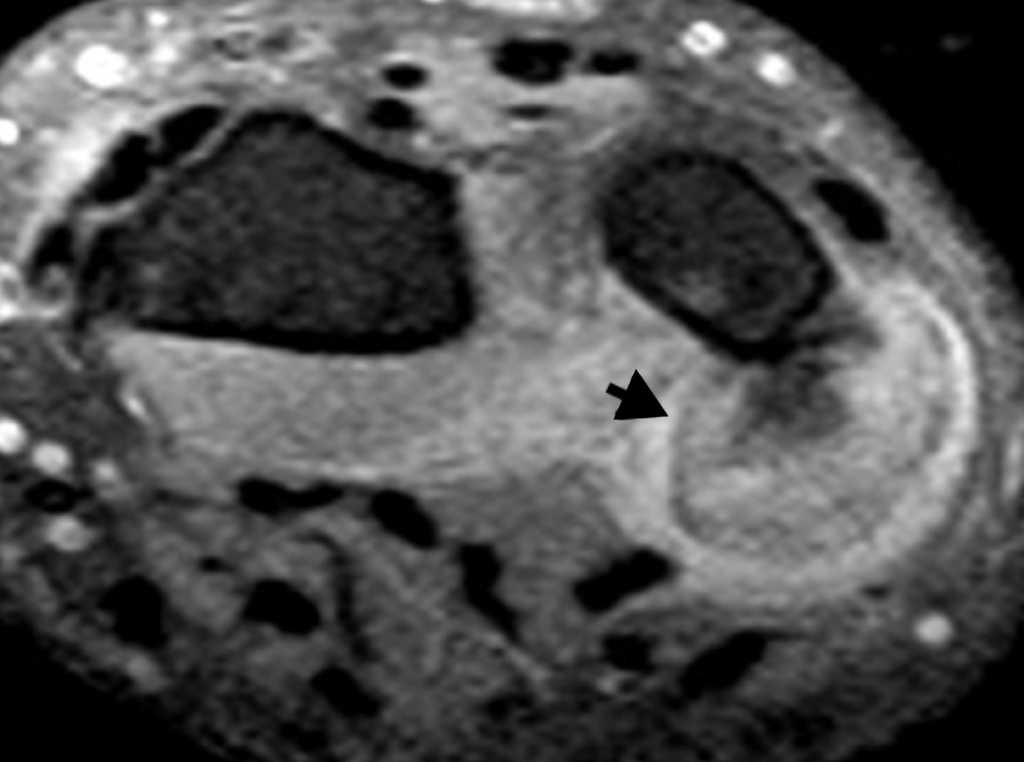

El primer caso se trató de un varón de 35 años con una tumoración en la cara volar de la muñeca derecha, presente desde hacía 2 años, pero que había crecido en los últimos meses. El paciente refería dolor en la muñeca e historia de traumatismo. La radiografía simple mostró una calcificación adyacente al extremo distal del cúbito, sin clara dependencia ósea (no mostrada); mientras que la tomografía computada (TC) corroboró la presencia de una lesión de localización metafisodiafisaria, que evidenciaba continuidad con la cortical ósea cubital posterior, sin afectación medular evidente. La lesión tenía márgenes bien definidos y matriz osteoide (fig. 1). La resonancia magnética (RM) constató la ausencia de afectación de la medular ósea (fig. 2) y el resultado de la biopsia confirmó la POPB.

La RM es muy útil para una mejor caracterización. Revela una lesión hipointensa en secuencias potenciadas en T1 e hiperintensa de forma variable en secuencias potenciadas en T2 y recuperación de inversión en tiempo corto (STIR), mostrando realce homogéneo tras la administración de contraste9.